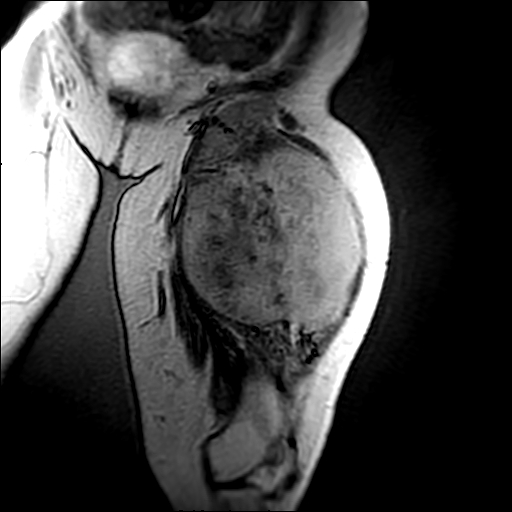

左侧大腿外伤10余年,当时情况不清,发现左侧大腿肿胀7年余,而后又有多次外伤史,近1年来出现疼痛,减重半年。查体:左侧大腿肿胀明显,皮温、肤色正常。

增强

软组织肿块,股骨破坏,增强不均匀强化-----支持恶性肿瘤